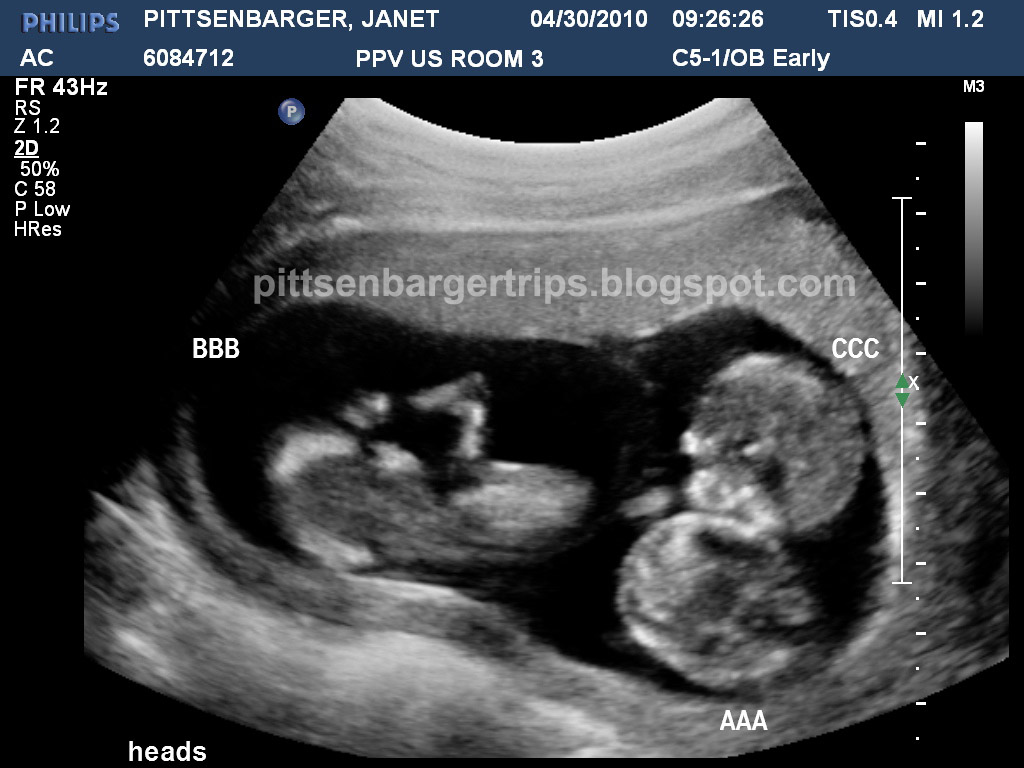

PITTS TRIP'S the Pittsenbarger identical triplets saga Identical Ultrasound Picture Of Triplets This ultrasound image actually shows triplets! Two thirds of triplet pregnancies. 3d ultrasound images of triplets gives an eery appearance to this rare medical phenomenon. Trichorionic triamniotic triplets (tcta) this sagittal view of the uterus show 3 individual gestational sacs. Each of the fetuses at 11 weeks has its. Marked with a, b, and c, this image captures three babies'. Ultrasound Picture Of Triplets.

PITTS TRIP'S the Pittsenbarger identical triplets saga 12 week Ultrasound Ultrasound Picture Of Triplets Trichorionic triamniotic triplets (tcta) this sagittal view of the uterus show 3 individual gestational sacs. It's very unusual for wiggly babies in utero to come together so. 3d ultrasound images of triplets gives an eery appearance to this rare medical phenomenon. The increased neonatal risks are primarily related to iatrogenic or spontaneous preterm birth: This ultrasound image actually shows triplets!. Ultrasound Picture Of Triplets.